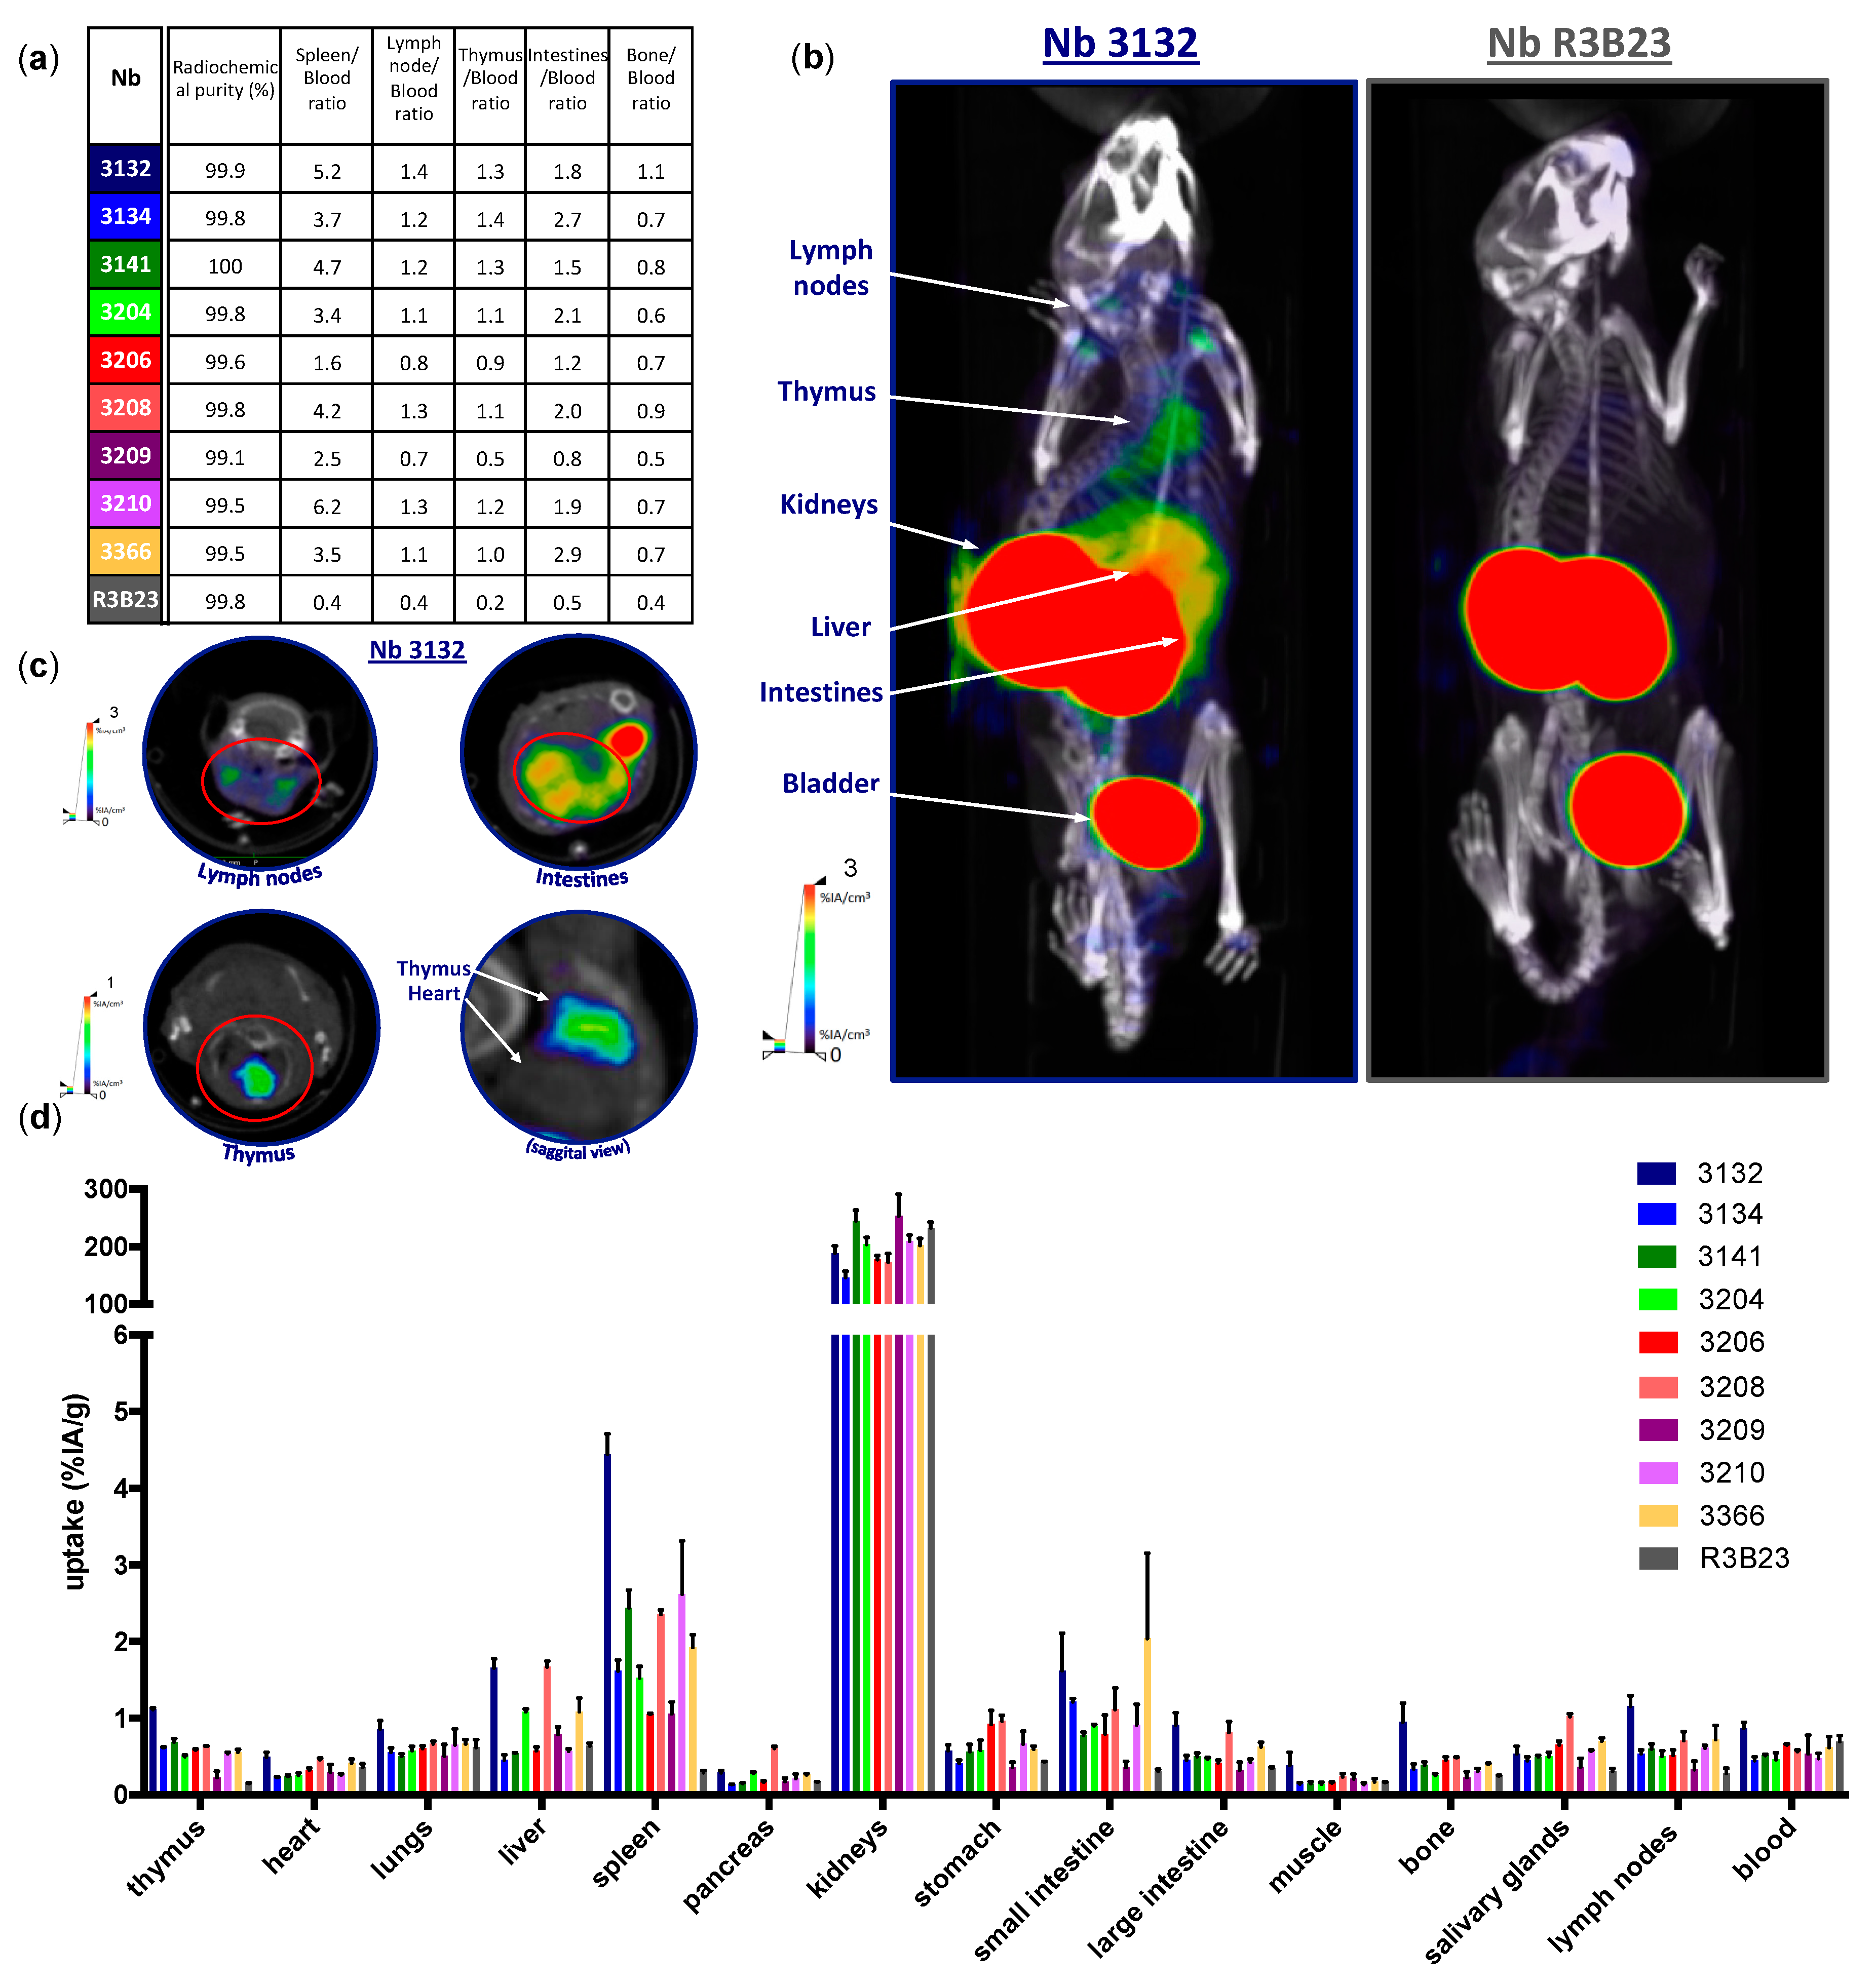

These results encourage the development of Nbs for molecular imaging of the inhibitory immune checkpoint receptor LAG-3. As this requires substantial preclinical evaluation, we developed and validated Nbs targeting mouse LAG-3 (moLAG-3) as probes for SPECT imaging. After alpaca immunization and biopanning via phage display, 114 Nbs were identified to bind recombinant LAG-3 protein. Bacterial extracts of these Nbs were further analyzed for binding to moLAG-3 using ELISA, flow cytometry and off-rate analysis using surface plasmon resonance (SPR). As such, nine moLAG-3 binding Nbs were selected. These Nbs were bacterially produced and purified, tested in flow cytometry, and their affinity was analyzed using SPR. Next, we labeled them with 99mTc, after which the biodistribution was assessed in immunocompetent and moLAG-3 gene-deficient mice by SPECT/CT imaging and dissection analyses. Subsequently, we evaluated the specific targeting of these Nbs in mice harboring tumors modified to overexpress mouse LAG-3.

31]. Mice used for imaging experiments, were injected intravenously with 100 µL of

99mTc-labeled Nbs (5 µg) with on average 51.1 ± 16.7 MBq of injected activity, 1 h before pinhole SPECT-micro-CT imaging. SPECT-CT imaging was performed using a Vector

+ scanner from MiLABS. SPECT imaging was performed with a 1.5 mm 75-pinhole general purpose collimator, in spiral mode with six bed positions, the total body SPECT scan time was 15 min, 150 s per position. The total CT-scan time was 139 s, set to 60 kV and 615 mA. After imaging, mice were sacrificed and organs were isolated to evaluate the organ-specific uptake of the tracer using a γ-counter (Cobra Inspector 5003, Canberra, Packard, Illinois, IL, USA). The tissue/organ uptake was corrected for decay and calculated as the percentage of injected activity per gram tissue (%IA/g). Image analysis was performed using HOROS medical imaging viewer (LGPL license at Horosproject.org) and AMIDE (Medical Image Data Examiner software, UCLA, California, CA, USA).

We showed that lymphocytes, residing in the lymph nodes of naive and healthy C57BL/6 mice, express low levels of moLAG-3. In contrast, lymph node residing antigen presenting cells expressed higher levels of moLAG-3. Within the spleen, the immune cell population (CD45

+) with the highest moLAG-3 expression could be detected on antigen-presenting cells, like dendritic cells and macrophages, and on NK and NKT cells [

4]. Moreover, very low amounts of moLAG-3 are expressed on CD19

+ B cells, and CD4

+ and CD8

+ T cells, which is comparable to the low levels found on lymphocytes isolated from lymph nodes. Nevertheless, out of nine different

99mTc-labeled anti-moLAG-3 Nbs, Nb 3132 was still able to detect and visualize low levels of moLAG-3 expressing immune cells residing in the spleen and lymph nodes. Although the affinity of Nb 3132 for moLAG-3 is rather low, injection of

99mTc-labeled Nb 3206, with a 10-fold higher affinity for moLAG-3, was less able to detect and image moLAG-3 expressing cells in the spleen and lymph nodes. Interestingly, when evaluating our Nbs for binding on moLAG-3 expressing cells using flow cytometry, Nb 3132 showed the highest binding of all Nbs. This observation could mean that recombinant moLAG-3 coated chips for SPR or membrane expressed LAG-3 for flow cytometry analysis are not completely identical and thus could lead to under or overestimation of Nb affinity. Moreover, the affinity of Nbs is only one of the parameters used to predict its potential for imaging purposes. Vaneycken et al. showed that the dissociation rate of Nbs did not correlate with tumor uptake since their Nb with the slowest dissociation rate targeted poorly to tumors, while another Nb, with a fast dissociation rate, targeted very well [

40]. Nevertheless, the specific uptake for

99mTc-labeled anti-moLAG-3 Nb 3132 and 3206 was further validated using LAG-3 KO mice, where no uptake could be detected in organs like spleen and lymph nodes, expect for the liver. However, the uptake of

99mTc-labeled Nb 3132 in the liver of LAG-3 KO was significantly lower compared than in LAG-3 WT mice, suggesting that accumulation was partly due to specific binding. To this date, no supportive data could be found in literature describing LAG-3 expression in the liver. Several studies have reported non-specific uptake of radiolabeled Nbs in the liver, explaining the remaining liver uptake in LAG-3 KO mice [

39]. Unfortunately, the nonspecific accumulation in the liver could obscure possible liver metastases and such accumulation should be taken into account when selecting Nbs for the noninvasive imaging of human LAG-3 since these are most likely to reach the clinic compared to moLAG-3 targeting Nbs.